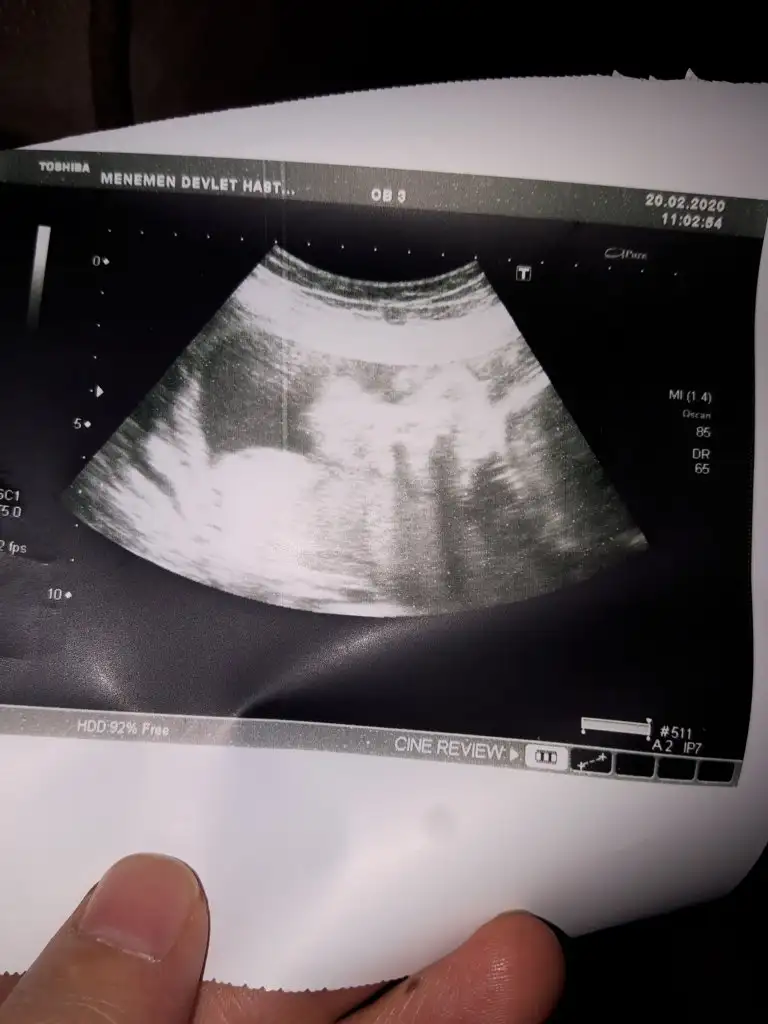

Merhaba ben yeni uyeyim şuan 9 haftalığız merakla bekliyoruz cinsiyeti tabiki önemli değil önemli olan sağlıklı hayırlı evlat olması ama bize de yorum yapar mısınız

Eklentiler

• 20200225_140739.webp

20200225_140739.webp

19,1 KB · Görüntüleme: 286